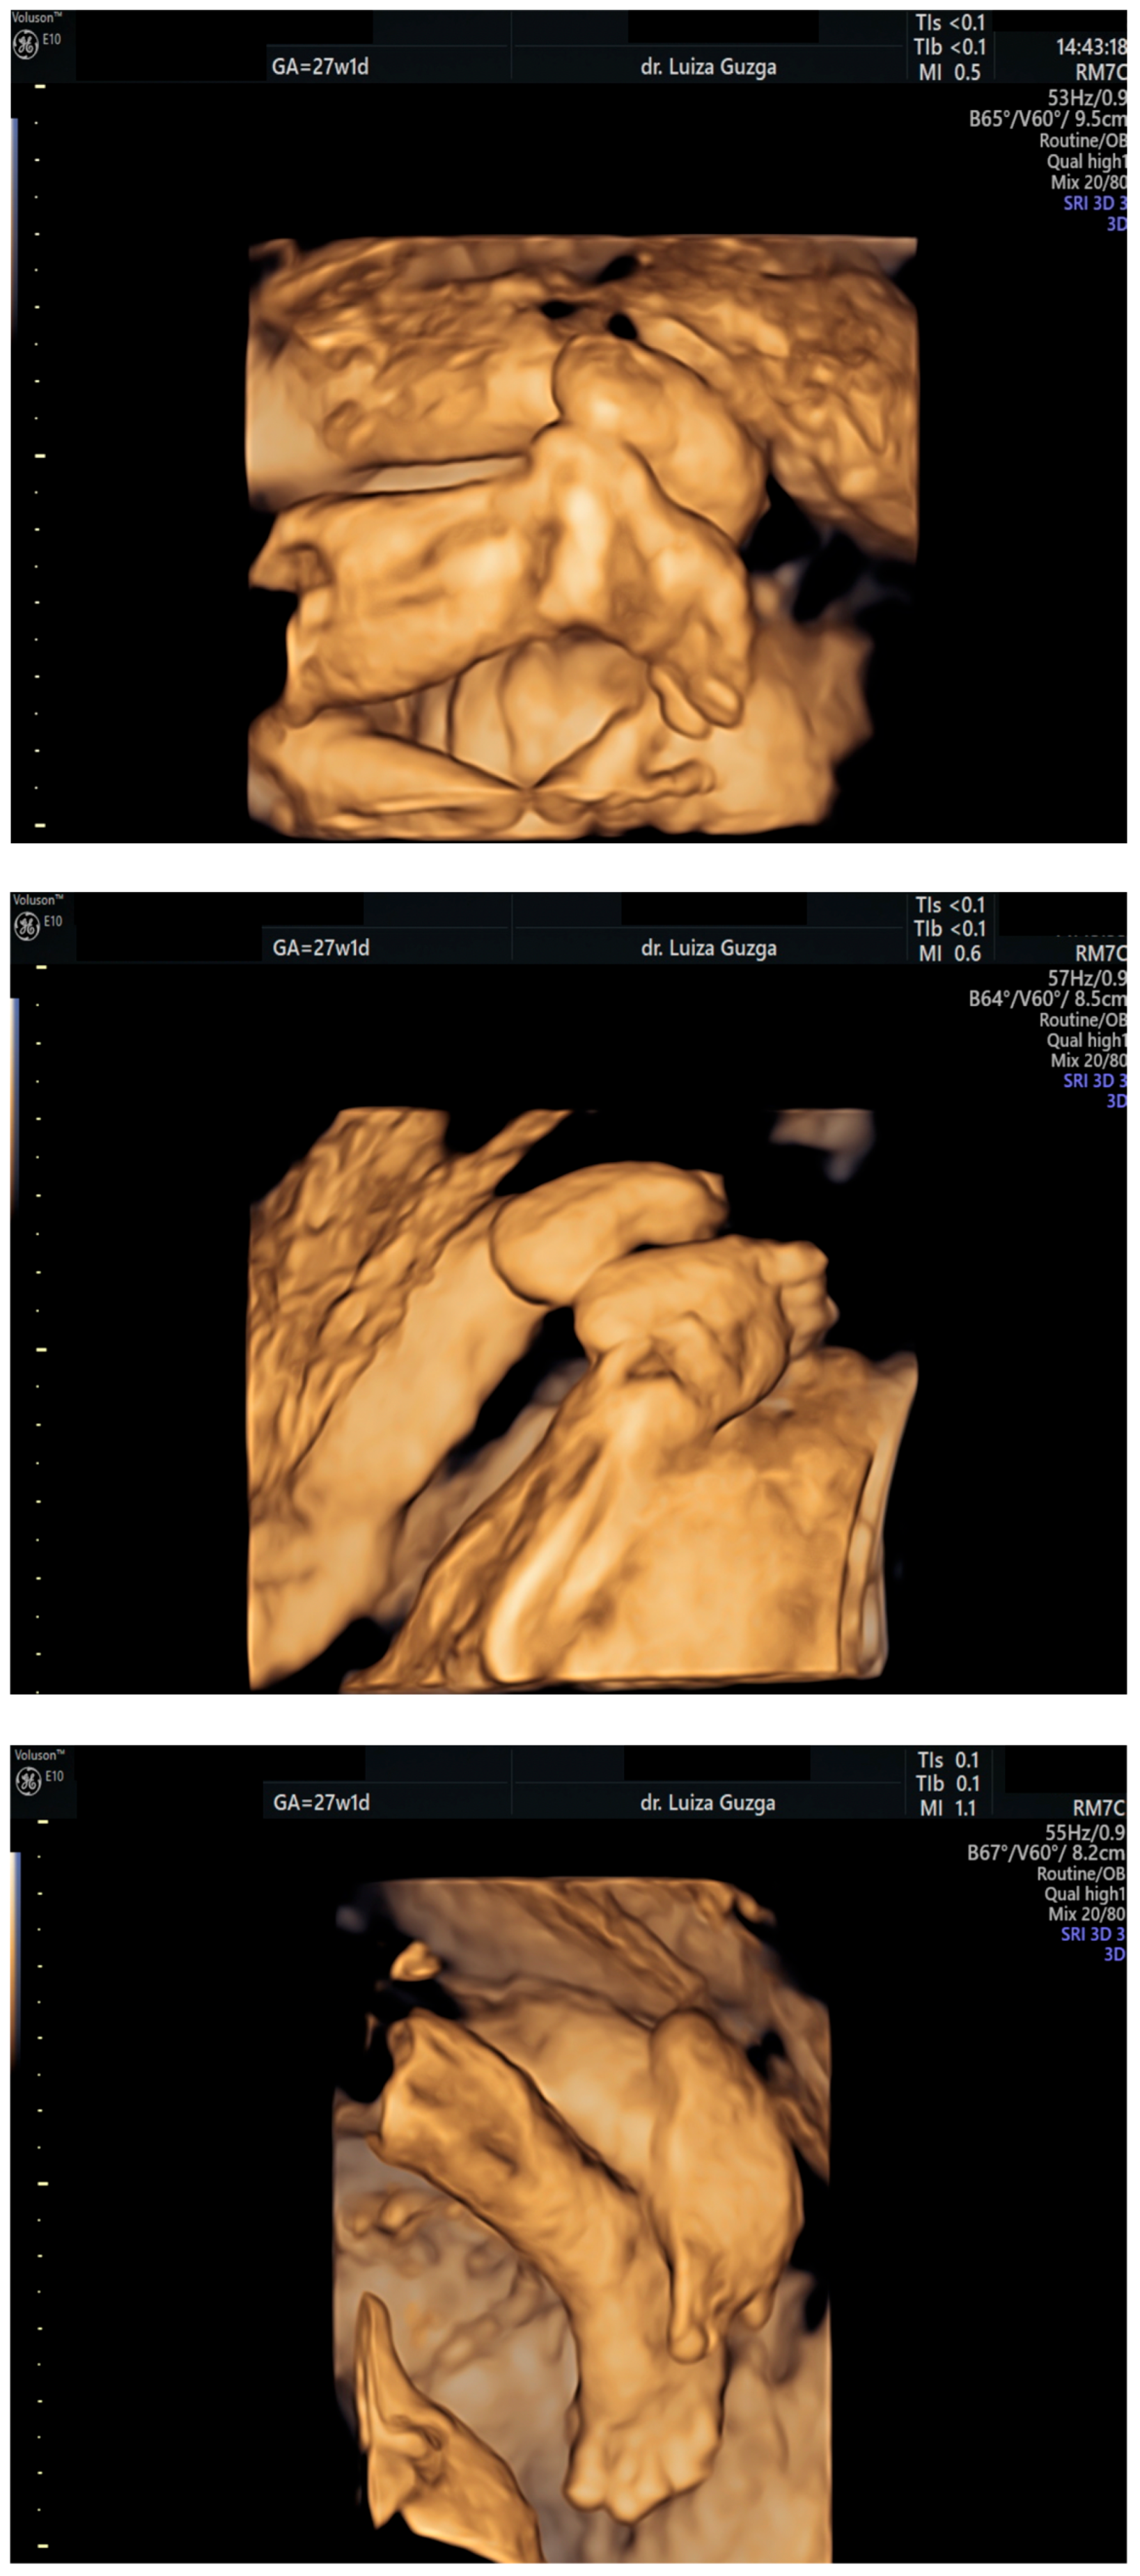

| Broad thumb | - | +++ | +++ | +++ |

| Rocker-bottom feet | - | +++ | +++ | +++ |